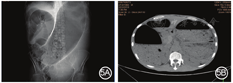

多是因为医疗原因造成结肠局部、或一段肠管发生狭窄或者无蠕动功能而导致近端慢性扩张而形成巨结肠。笔者治疗过的1例因降结肠癌术后吻合口狭窄导致的巨结肠患者,将狭窄吻合口及近端部分巨结肠切除后痊愈。另有1例因慢性便秘患者于当地医院行结肠造口术并于2年后还纳造口,因吻合口狭窄导致近端形成巨结肠,以梗阻症状急诊来院检查发现,近端肠腔极度扩张,压迫膈肌及纵隔,经肠镜减压未好转,转而行肠减压术+结肠造口术,见图4。此外,临床上,低位直肠癌患者由于术前或者术后放疗导致直肠壁僵硬或直肠周围瘢痕增生以及蠕动功能降低的情况越来越多,进而引起近端肠腔慢性扩张形成巨结肠,此类患者易反复出现腹胀症状,部分患者甚至因急性梗阻来院就诊,保守治疗(如肠镜减压、留置肛管)可暂时缓解症状,但最终仍需行永久性肠造口,见图5。